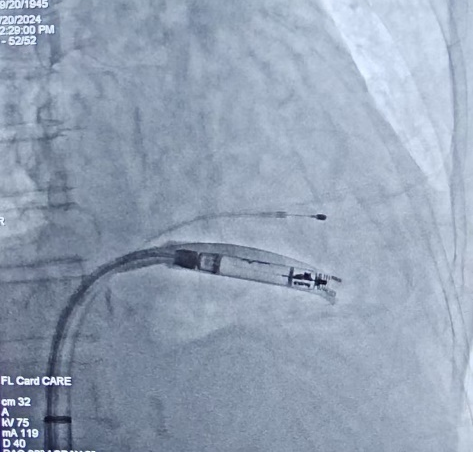

在充分抗感染治疗后,9月20日在局麻下,桂春主任成功为刘女士植入一台长寿命(15年)可回收主动固定的AVEIR无导线心脏起搏器。这也是全国首批电极拔除术后AVEIR无导线起搏器植入手术在我院成功开展。

图片 图片 ▲无导线起搏器植入的X线影像